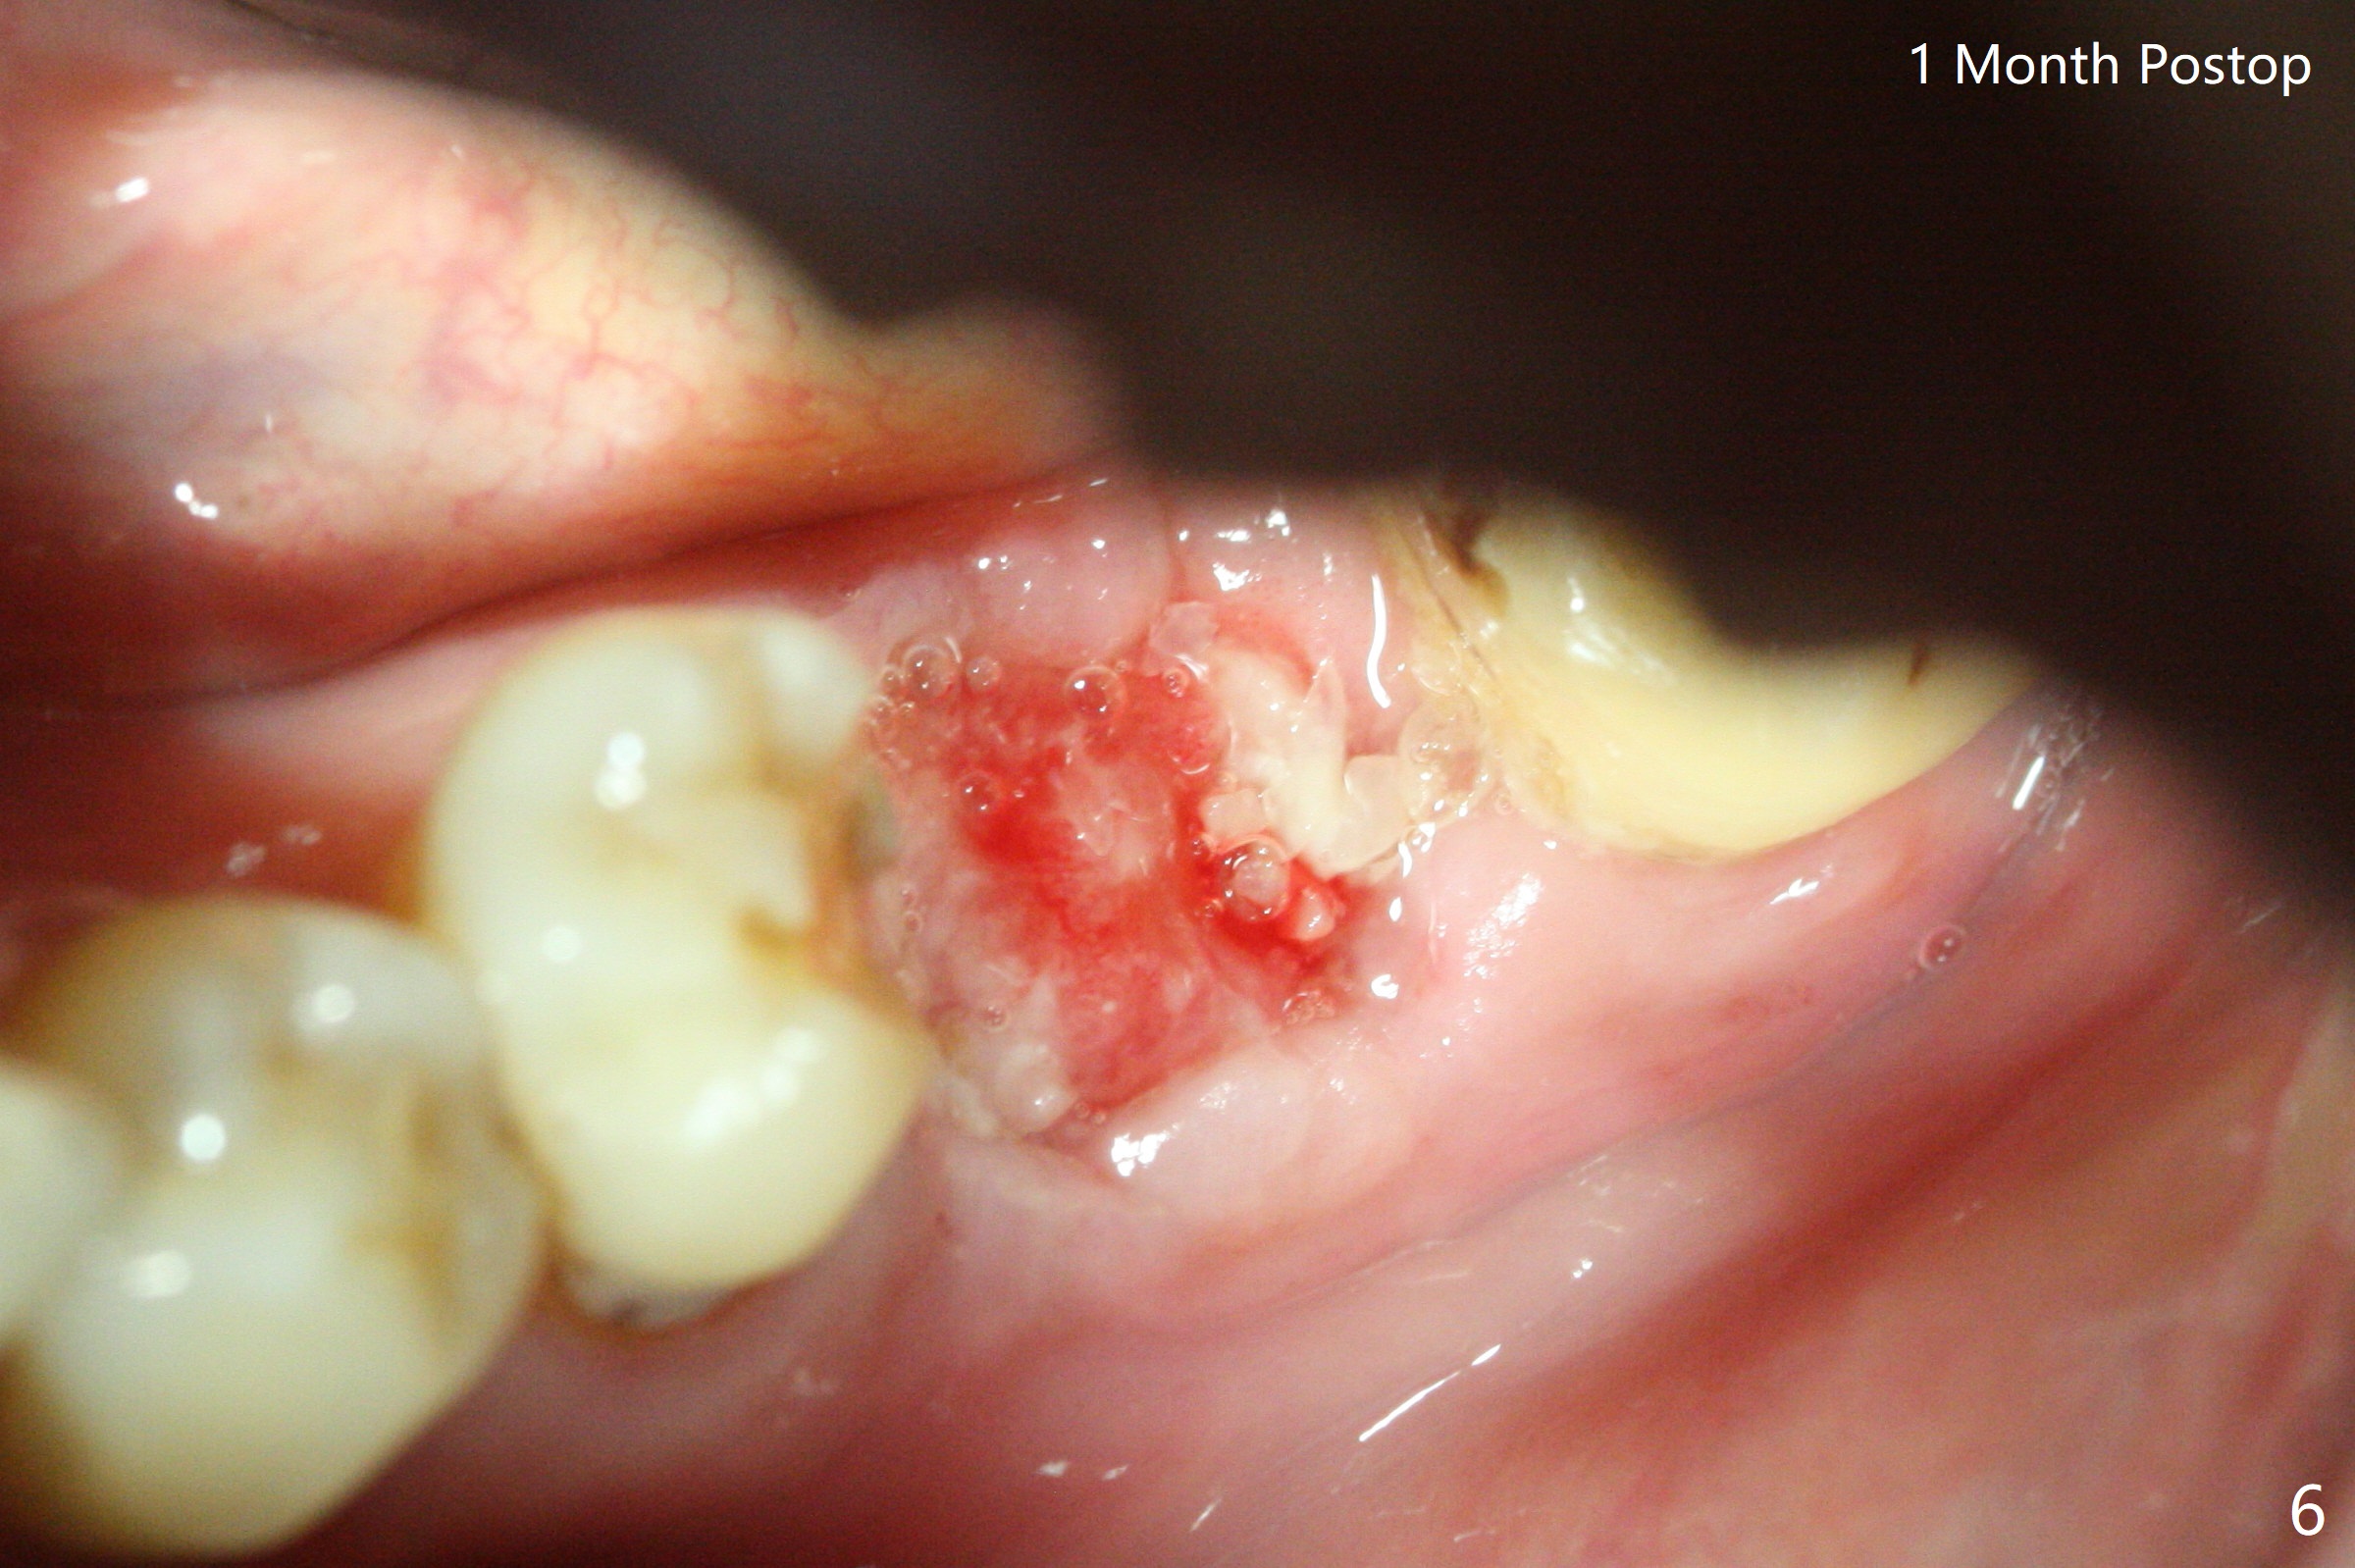

A 73-year-old man (with history of lung cancer with chemotherapy 6 years ago) requests removing the tooth #19 (Fig.1) with the loose mesiolingual fragment (Fig.2 ML). The mesiobuccal plate is low when the tooth is extracted. The septum should provide additional blood supply to bone graft to facilitate healing (Fig.3 S, as compared to the case without it). After placement of 6-month membrane and suturing, acrylic dressing is applied, which is stable 9 days postop (Fig.4 A). The acrylic dressing remains in place 1 month postop (Fig.5). After wiggling, it dislodges fairly easily. The socket heals with slight atrophy (Fig.6).